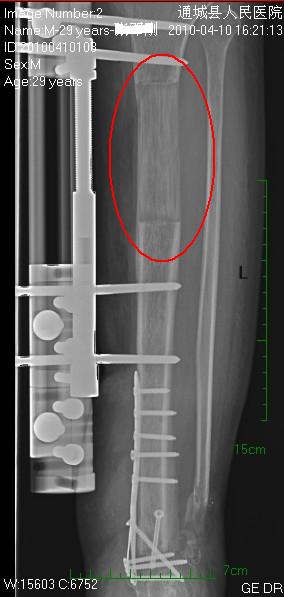

该患者车祸致小腿多发性骨折行内固定术后。因胫骨上段骨折处事后感染再行病灶段截取,采用外延长支架牵拉骨延长术,逐步牵拉已一年余,所见延长段长8.8cm(图文工作站上所测),并无自体植骨或人工材料充填。此次为遵嘱拍片寄往上海某施术医院复查。

以前没见过截骨延长病例的平片资料,与日常的常见的骨折后骨痂、骨膜反应、骨化性肌炎之类的影像有形态上区别,虽仅此一例不能概全,但也可让我们有个印象,特呈上以飨同仁。[em2]